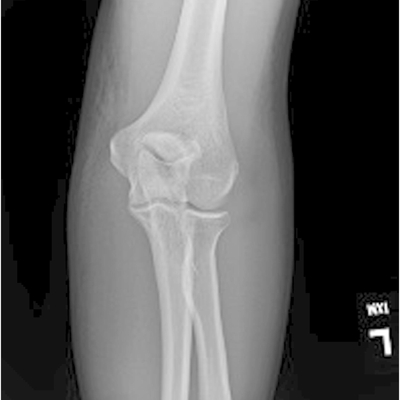

Click on an image below to view more info.